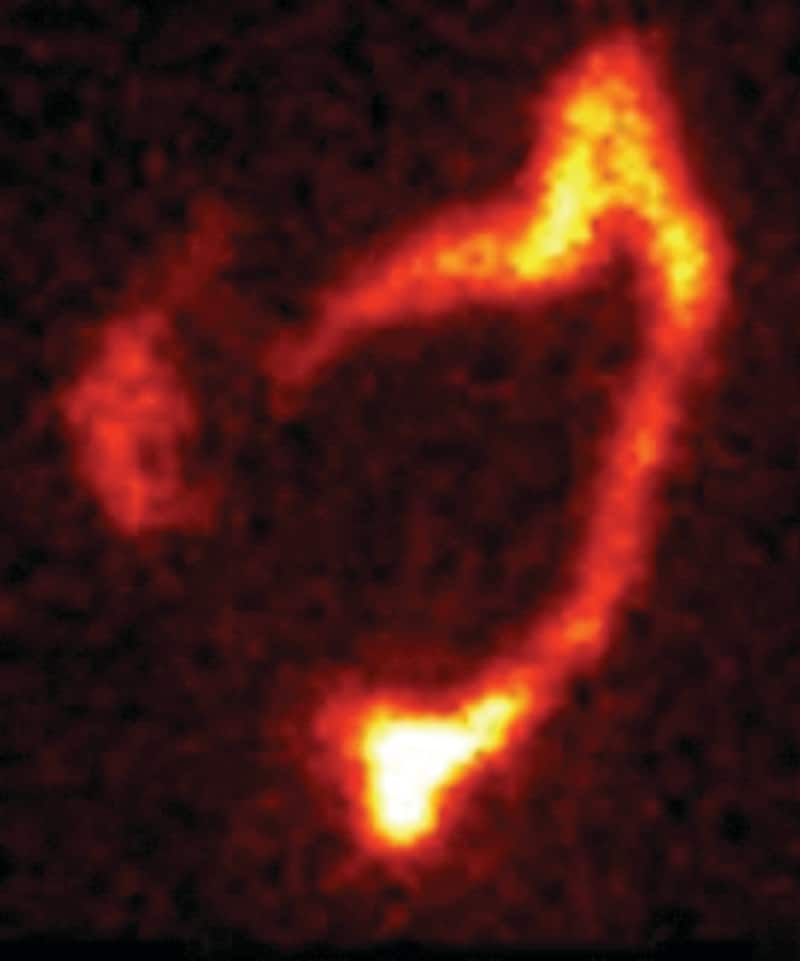

洗腸後

シンチグラフィーの画像について

脊髄損傷患者さんと神経因性大腸機能障害を有する患者さんに対して実施されたシンチグラフィーを用いた研究において、経肛門的洗腸療法は、腸管内容物を排出するのに有効であることが示されました。1

1回の経肛門的洗腸療法によって直腸から下行結腸までの便を排出することで、新たな便が直腸に到達するまでの1~2日間、便失禁を防ぐことが出来ます。1,2

1. Christensen P, Olsen N, Krogh K, Bacher T, Laurberg S. Scintigraphic assessment of retrograde colonic washout in fecal incontinence and constipation. Dis Colon Rectum 2003;46:68–76.